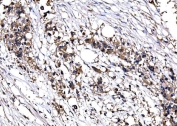

IHC staining of FFPE human renal cell carcinoma tissue with IMPDH1 antibody. HIER: boil tissue sections in pH8 EDTA for 20 min and allow to cool before testing.

IHC staining of FFPE human splenic rupture tissue with IMPDH1 antibody. HIER: boil tissue sections in pH8 EDTA for 20 min and allow to cool before testing.

IHC staining of FFPE human breast cancer tissue with IMPDH1 antibody. HIER: boil tissue sections in pH8 EDTA for 20 min and allow to cool before testing.

IHC staining of FFPE human lymphoma tissue with IMPDH1 antibody. HIER: boil tissue sections in pH8 EDTA for 20 min and allow to cool before testing.

IHC staining of FFPE human colon adenocarcinoma tissue with IMPDH1 antibody. HIER: boil tissue sections in pH8 EDTA for 20 min and allow to cool before testing.